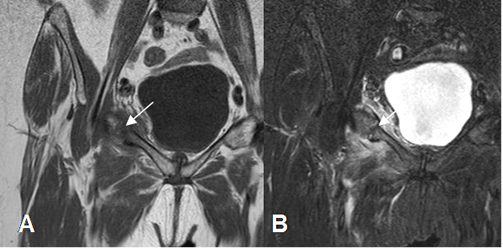

Fig 75. Fractura de stress.

A: RM coronal en T1 y B: RM coronal en STIR. Igual paciente anterior. También existe fractura no desplazada, en el ramo iliopúbico derecho. (Flechas).